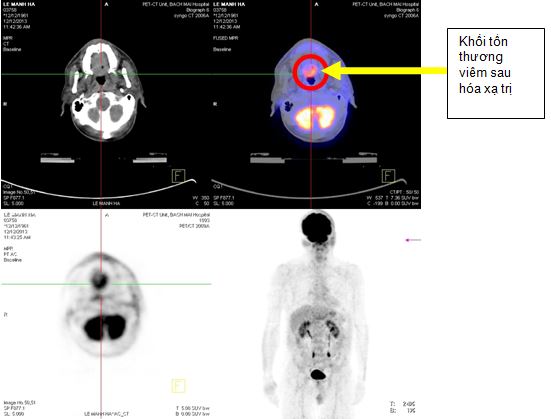

Bệnh nhân được chụp PET/CT với hai mục đích: đánh giá mức độ xâm lấn, di căn của khối u và dùng hình ảnh PET/CT để mô phỏng lập kế hoạch xạ trị

Trên hình ảnh PET/CT:

- Vùng đáy lưỡi có khối lớn kéo dài đến thanh quản kích thước: 2,4x3,6x2,9cm, tăng hấp thu F18- FDG max SUV=8,28.

- Hạch góc hàm trái kích thước: 1,9cm, tăng hấp thu F18- FDG max SUV=6,89. Hạch góc hàm phải kích thước: 1,8cm, max SUV=5,28. Hạch cảnh giữa phải kích thước: 1,3cm, max SUV=4,42.

Hình 3. Hình ảnh khối u vùng đáy lưỡi di căn hạch cổ hai bên trên hình ảnh PET/CT

+ Tháng 12 năm 2013, bệnh nhân được chup PET/CT lần 2 sau khi kết thúc xạ trị và 4 đợt hoá trị. Trên hình ảnh PET/CT cho thấy: vùng đáy lưỡi có khối tăng hấp thu F-18 FDG, kích thước 3,9x4,3x3,0cm, theo dõi tổn thương viêm sau xạ trị. Không thấy hạch cổ tăng hấp thu F-18 FDG bất thường.

Hình 6. Hình ảnh PET/CT sau xạ trị 70Gy và 4 đợt hoá trị